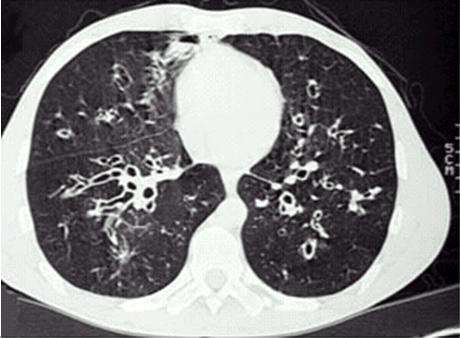

支气管扩张